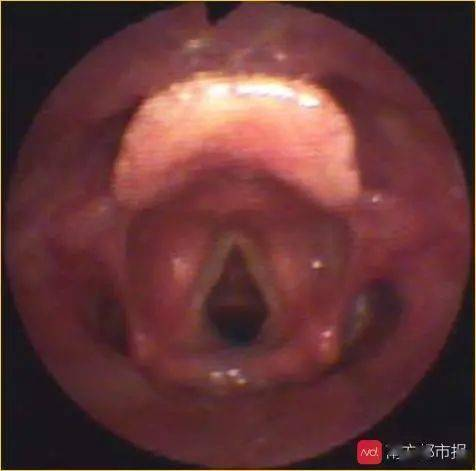

卷曲的会厌软骨遮挡声门 正常会厌软骨及声门

慢性间歇性发作的婴幼儿喉喘呜最常见的病因是喉软化,一般发生于生后数周出现,1岁左右自愈。但是如果婴幼儿出现慢性持续性加重性喉鸣,需要进行颈部、肺部增强CT及气道重建检查、心脏彩超、电子喉镜及支气管镜等检查辅助检查以明确是否存在咽喉部囊肿、血管瘤及声门下狭窄等疾病。